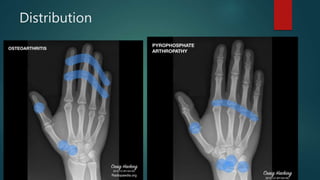

Distribution